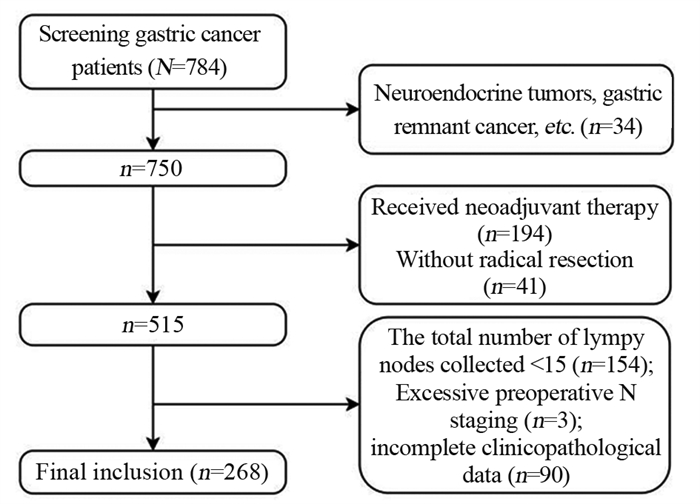

方法回顾性分析268例胃癌患者的临床病理资料。患者术前常规行薄层增强CT评估术前N分期,结合术后病理结果分析术前N分期不足的危险因素。Logistic回归分析筛选出的影响因素,Kaplan-Meier绘制术前N分期准确组与不足组的生存曲线,利用R软件包绘制Nomogram图、预测模型的ROC曲线,计算AUC、95%CI、敏感度和特异性。

MethodsA retrospective method was used to analyze the clinicopathological data of 268 patients with gastric cancer. The patients routinely underwent preoperative thin-section enhanced CT to assess preoperative N-stage. Results The risk factors for preoperative N-stage deficiency were analyzed in combination with postoperative pathological findings. Multifactorial logistic regression analysis was performed to determine influencing factors, and Kaplan-Meier analysis was used to plot the survival curves of preoperative N-stage accurate group and deficiency group. The nomogram plot and ROC curves of the prediction model were drawn using the R package. AUC, 95%CI, sensitivity, and specificity were calculated.